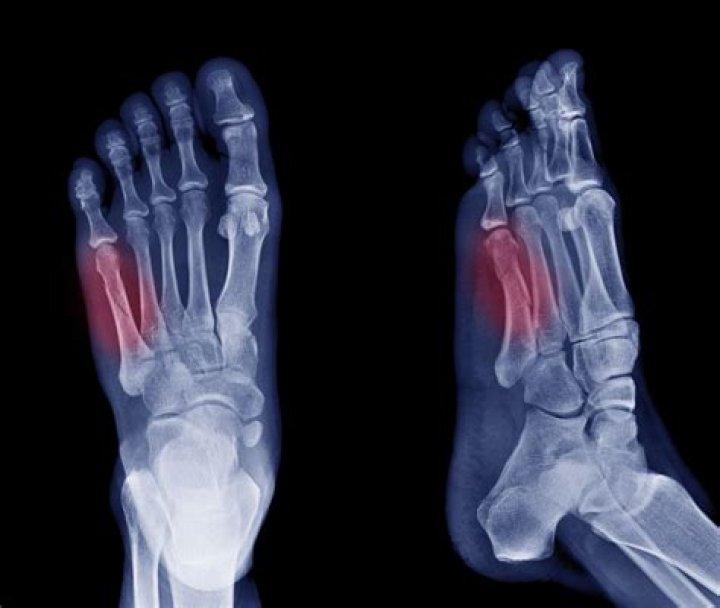

Can you walk on a fractured foot?

Typically you can walk on a broken foot, however, doing so will aggravate the situation. It's best to give your foot a rest, and keep weight off it, so that bones can take the time they need to heal. It is always best to get an injury like a fracture checked out to ensure proper treatment.

Do fractures show up right away?

Stress fractures often can't be seen on regular X-rays taken shortly after your pain begins. It can take several weeks — and sometimes longer than a month — for evidence of stress fractures to show on X-rays. Bone scan.